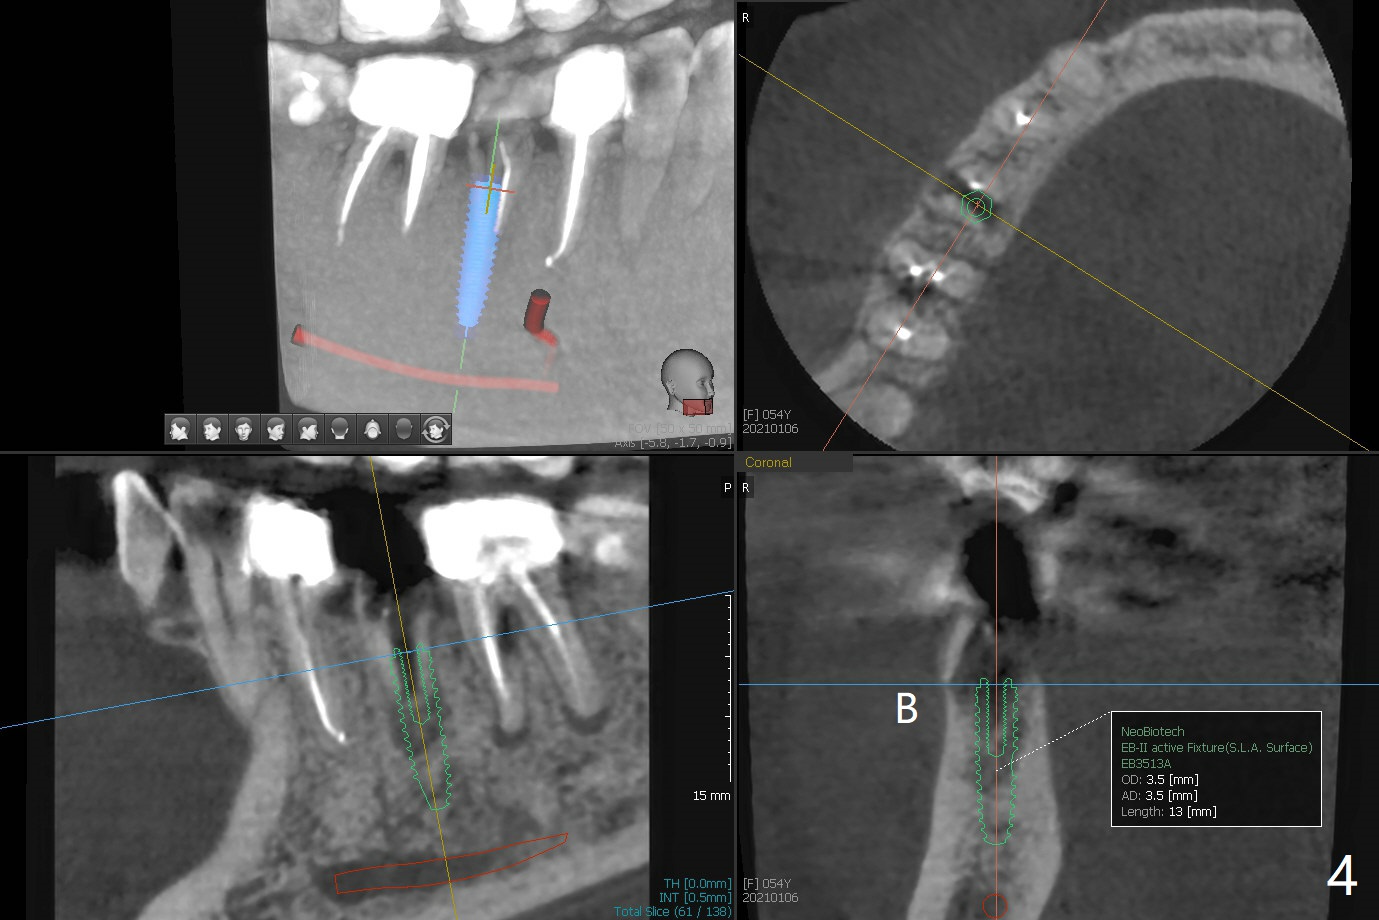

今天遇见一位特殊病人,54岁女,“右下一个牙齿断裂,我觉得一定要拔 (图一:5)。能不能同时种牙,减少痛苦。不过你是医生,一切由你决定”。为了炫耀,介绍导板,她还没有提钱的问题,估计必须再等十年才能碰见怎么有远见的土豪(夸张)。所以我们迫不及待拍摄CT,然后取模。至今有没有不对的地方,尤其是拍摄CT。要做导板周围(前后)有牙冠,在拍摄CT下,会产生折射(图二:*),影响CT精确度,不能与口内模型互相融合,从而影响导板精确度。如果实在想做导板,必须事先在牙冠上制作树脂cone(图三:红色三角形),然后拍摄CT和取模(或者scan),实验员才能准确融合两个图像。对于这个病例,只能做徒手种植,减少射线。不过增加手术时间,为了不损伤颏神经(图四),可能需要多次拍摄根尖片,增加无限的烦恼,一失足成千古恨。但是不会失去最后一个手段:PRF。